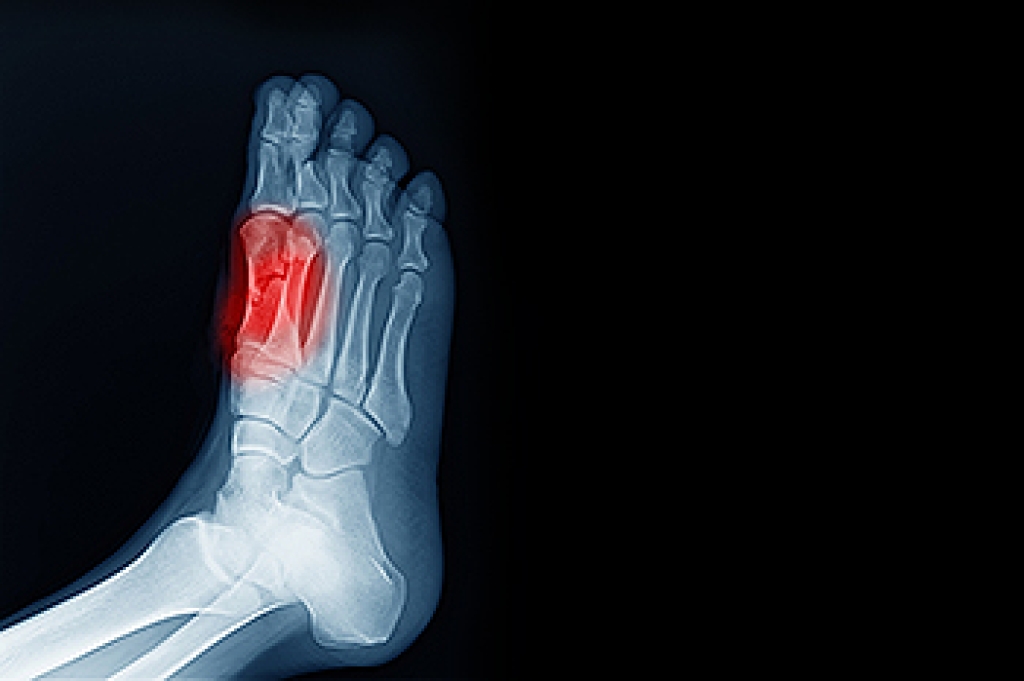

Plantar warts are the result of HPV, or human papillomavirus, getting into open wounds on the feet. They are mostly found on the heels or balls of the feet.

- Wart seeds, which are small clotted blood vessels that look like little black spots